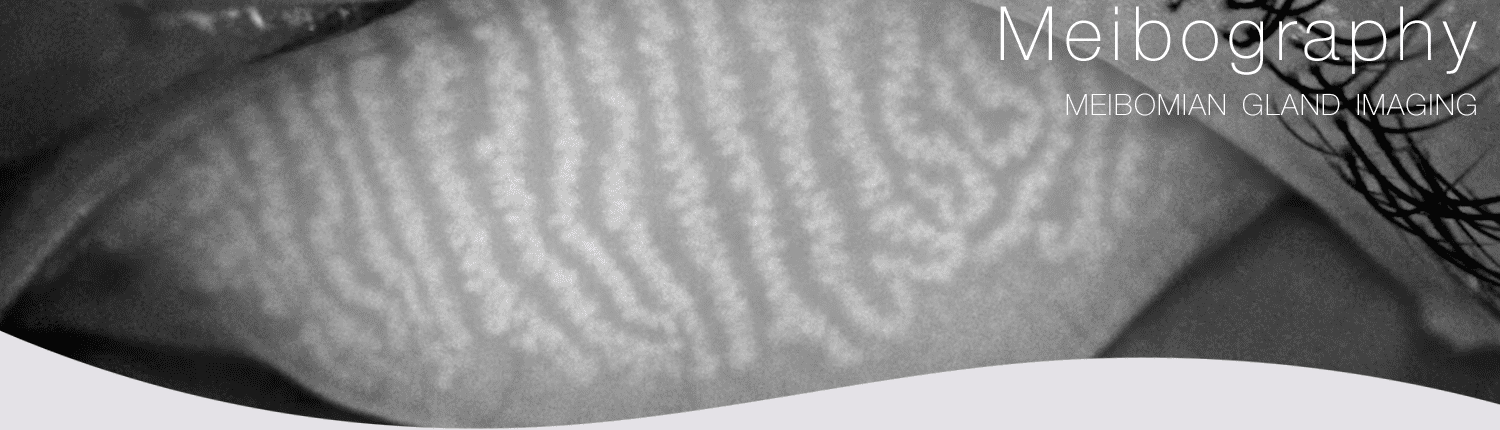

Meibography is a diagnostic test that is used to visualize the meibomian glands in the eyelids. The meibomian glands are located in the eyelids and produce oil (meibum) that helps to keep the surface of the eye lubricated. When these glands become blocked or infected, it can cause a variety of symptoms, including dry eye, eye irritation, and inflammation of the eyelids.

Meibography is performed using a specialized camera that takes images of the meibomian glands. The camera uses infrared light to create a detailed image of the glands, which can help the doctor to identify any abnormalities or blockages. Meibography is usually performed as an outpatient procedure, and the patient can usually return to their normal activities the same day.

Meibography is a useful tool for diagnosing and managing meibomian gland dysfunction, a common cause of dry eye. It is also used to monitor the effectiveness of treatment for dry eye and to guide the placement of punctal plugs, which are small devices that are inserted into the tear ducts to help retain moisture in the eye.